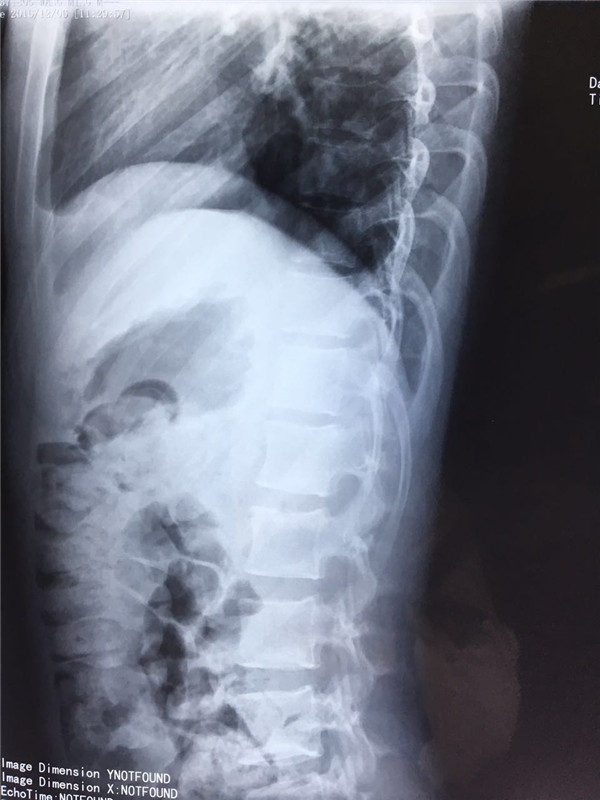

术前 正位

术前 侧位